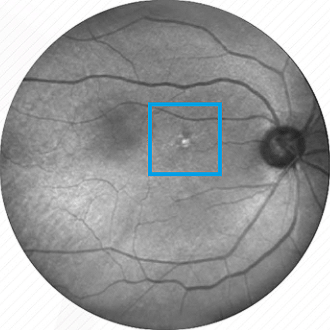

Diabetes

Auf der Netzhaut sind Blutungen und Gefäßveränderungen zu sehen, die meist bei einer Zuckererkrankung beobachtet werden.